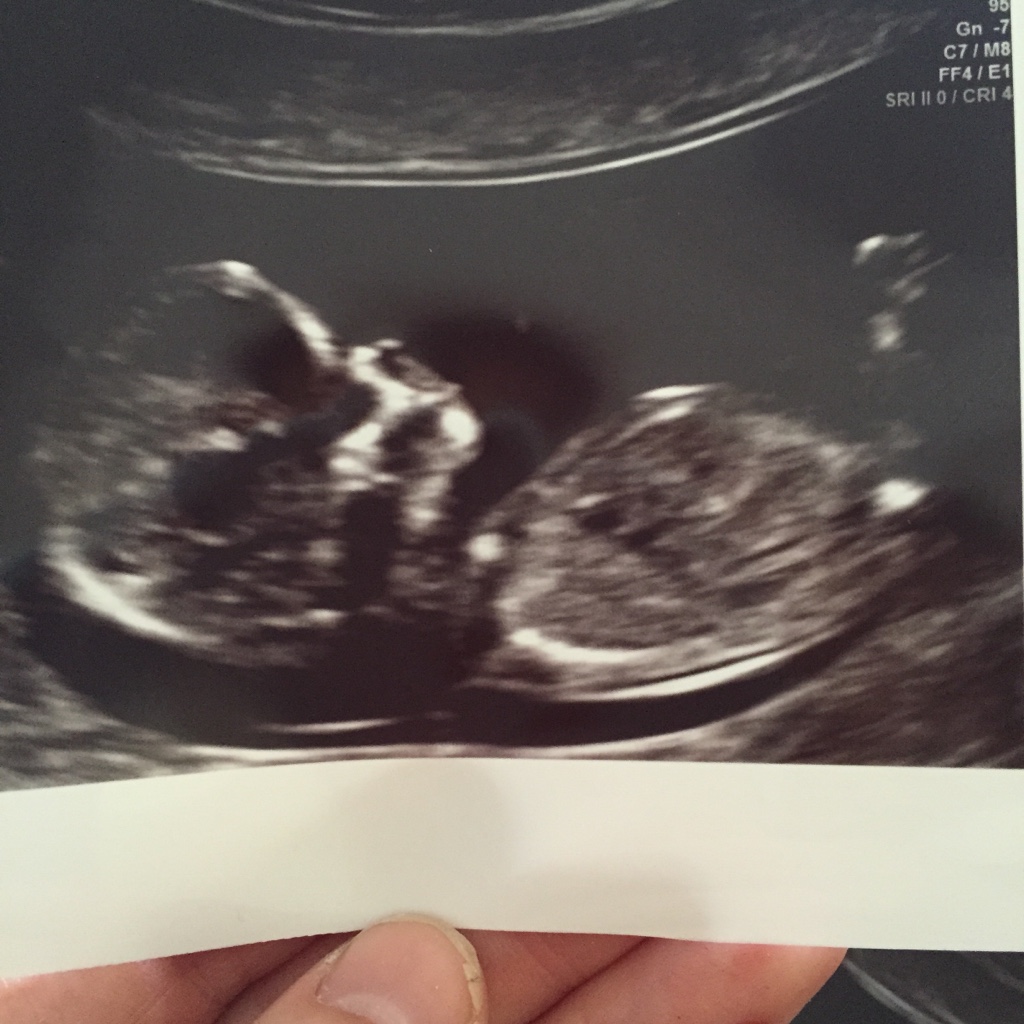

12+3 gender guesses

So this is my 12+3 scan pic from this morning. I never seem to get a good nub shot on any scans buying know you lot are good. I was leaning girl when I was having the actual scan but now not so sure. Would love to hear your thoughts? ️Xxx

I think I would give a slight boy lean based on those pics, what are you hoping for?

Leaning boy based on first pic

Sorry we can't tell you girl. It really does look like boy to me. Congrats on pregnancy!